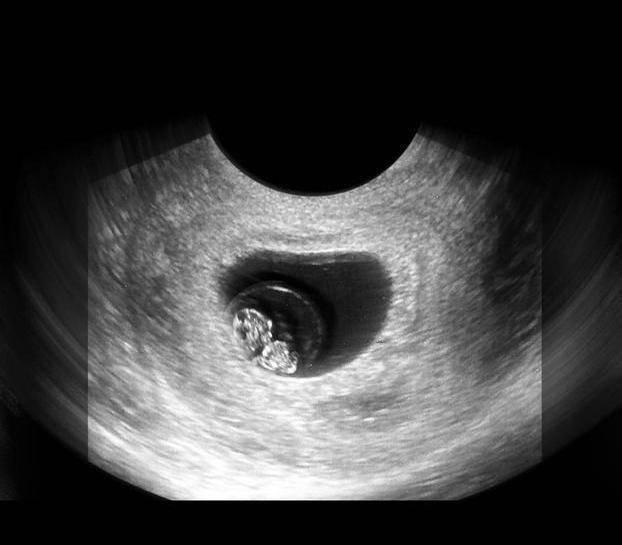

文章插图

在上图可见是个双胎妊娠,胎儿具有一个很大的头,和身材很不对称,是不是跟出生后的胎宝宝有点像了?其实此时的头部比例更悬殊,宝宝的额面部器官发育很明显,心脏也开始了跳动,出现了胎心,此时做B超,可见胎心胎芽。